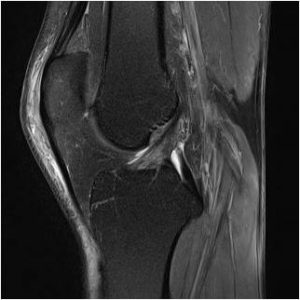

Diagnosis

MRI scan